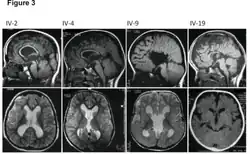

MRI images showing megalencephaly in four family members who all have unusually large skulls (the family is affected by an autosomal recessive syndrome caused by a KIF7 mutation that induces multiple epiphyseal dysplasia)[1] | |